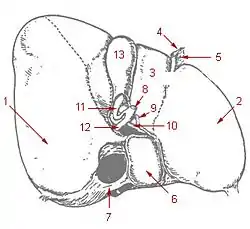

1: Right lobe of liver 2: Left lobe of liver 3: Quadrate lobe of liver 4: Round ligament of liver 5: Falciform ligament 6: Caudate lobe of liver 7: Inferior vena cava 8: Common bile duct 9: Hepatic artery 10: Portal vein 11: Cystic duct 12: Common hepatic duct 13: Gallbladder | |